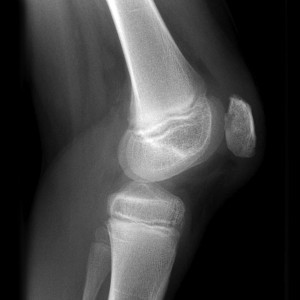

Надколенник находится на фронтальной части коленного сустава в пателлофеморальной канавке. Сверху сесамовидная кость закреплена к сухожилию четырехглавой мышцы бедра, а снизу – собственными связками к бугристости большеберцовой кости. Кость имеет треугольную форму, верхушка которой развернута вниз, переднюю и заднюю поверхности.

Задняя часть соединяется с бедренной костью двумя фасетками:

- медиальной – образует сустав с медиальным мыщелком;

- латеральная – входит в сустав с наружным мыщелком.

Снимки в прямой, боковой и аксиальной проекциях позволяют установить степень перелома и выявить другие травмы. МРТ или КТ используются по показаниям, если травмируются мягкие ткани и другие компоненты сустава.